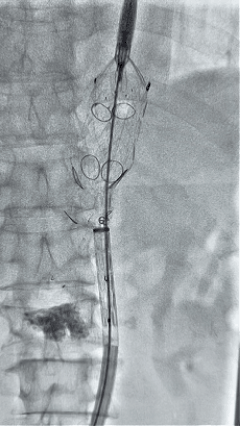

3. 经右股动脉导入超硬导丝,然后导入先健G-Branch 胸腹主动脉主体覆膜支架TAAA3418120e7i1010 一枚,释放主体支架至内分支打开,然后经左侧肱动脉入路,抓捕预置导丝成功后,将长鞘进入内分支出口处。

4. 经长鞘导入导管后,超选入腹腔干动脉,送入先健覆膜支架10*80mm一枚,近端重叠内分支,远端重叠腹腔干动脉,并予以10mm球囊后扩,手推造影显影良好。

5. 撤出腹腔干导丝导管,经左肱动脉长鞘继续抓捕预置导丝将长鞘超选至另一侧内分支,后超选进肠系膜上动脉,沿导丝送入先健覆膜支架10*100mm一枚,近端重叠内分支,远端重叠于肠系膜上动脉,并予以10mm球囊后扩,手推造影显影良好。

6. 解除束径,打开近端后释放,经肱动脉长鞘超选支架外分支,并进一步超选右侧肾动脉,交换加硬导丝,送入覆膜支架6*50mm和7*60mm各一枚,并予以球囊后扩张,手推造影显影良好。

7. 经长鞘重新选入左侧外分支,并超选进左肾动脉,沿导丝送入外周血管覆膜支架7*60mm一枚,并予以球囊后扩张,手推造影显影良好。

8. 从右侧股动脉入路送入腹主支架AB-24-12-110-S,近端重叠胸腹主动脉支架远端,调整好支架位置后释放。

9. 经左股动脉送入导丝导管,超选进腹主动脉支架短腿内,后沿导丝送入髂支,同理,右侧沿导丝送入髂支并释放,使用先健顺应性球囊后扩各支架连接处及支架近远端,最后通过预留导管向瘤腔注入人纤维蛋白粘合剂数支,造影显示分支通畅。